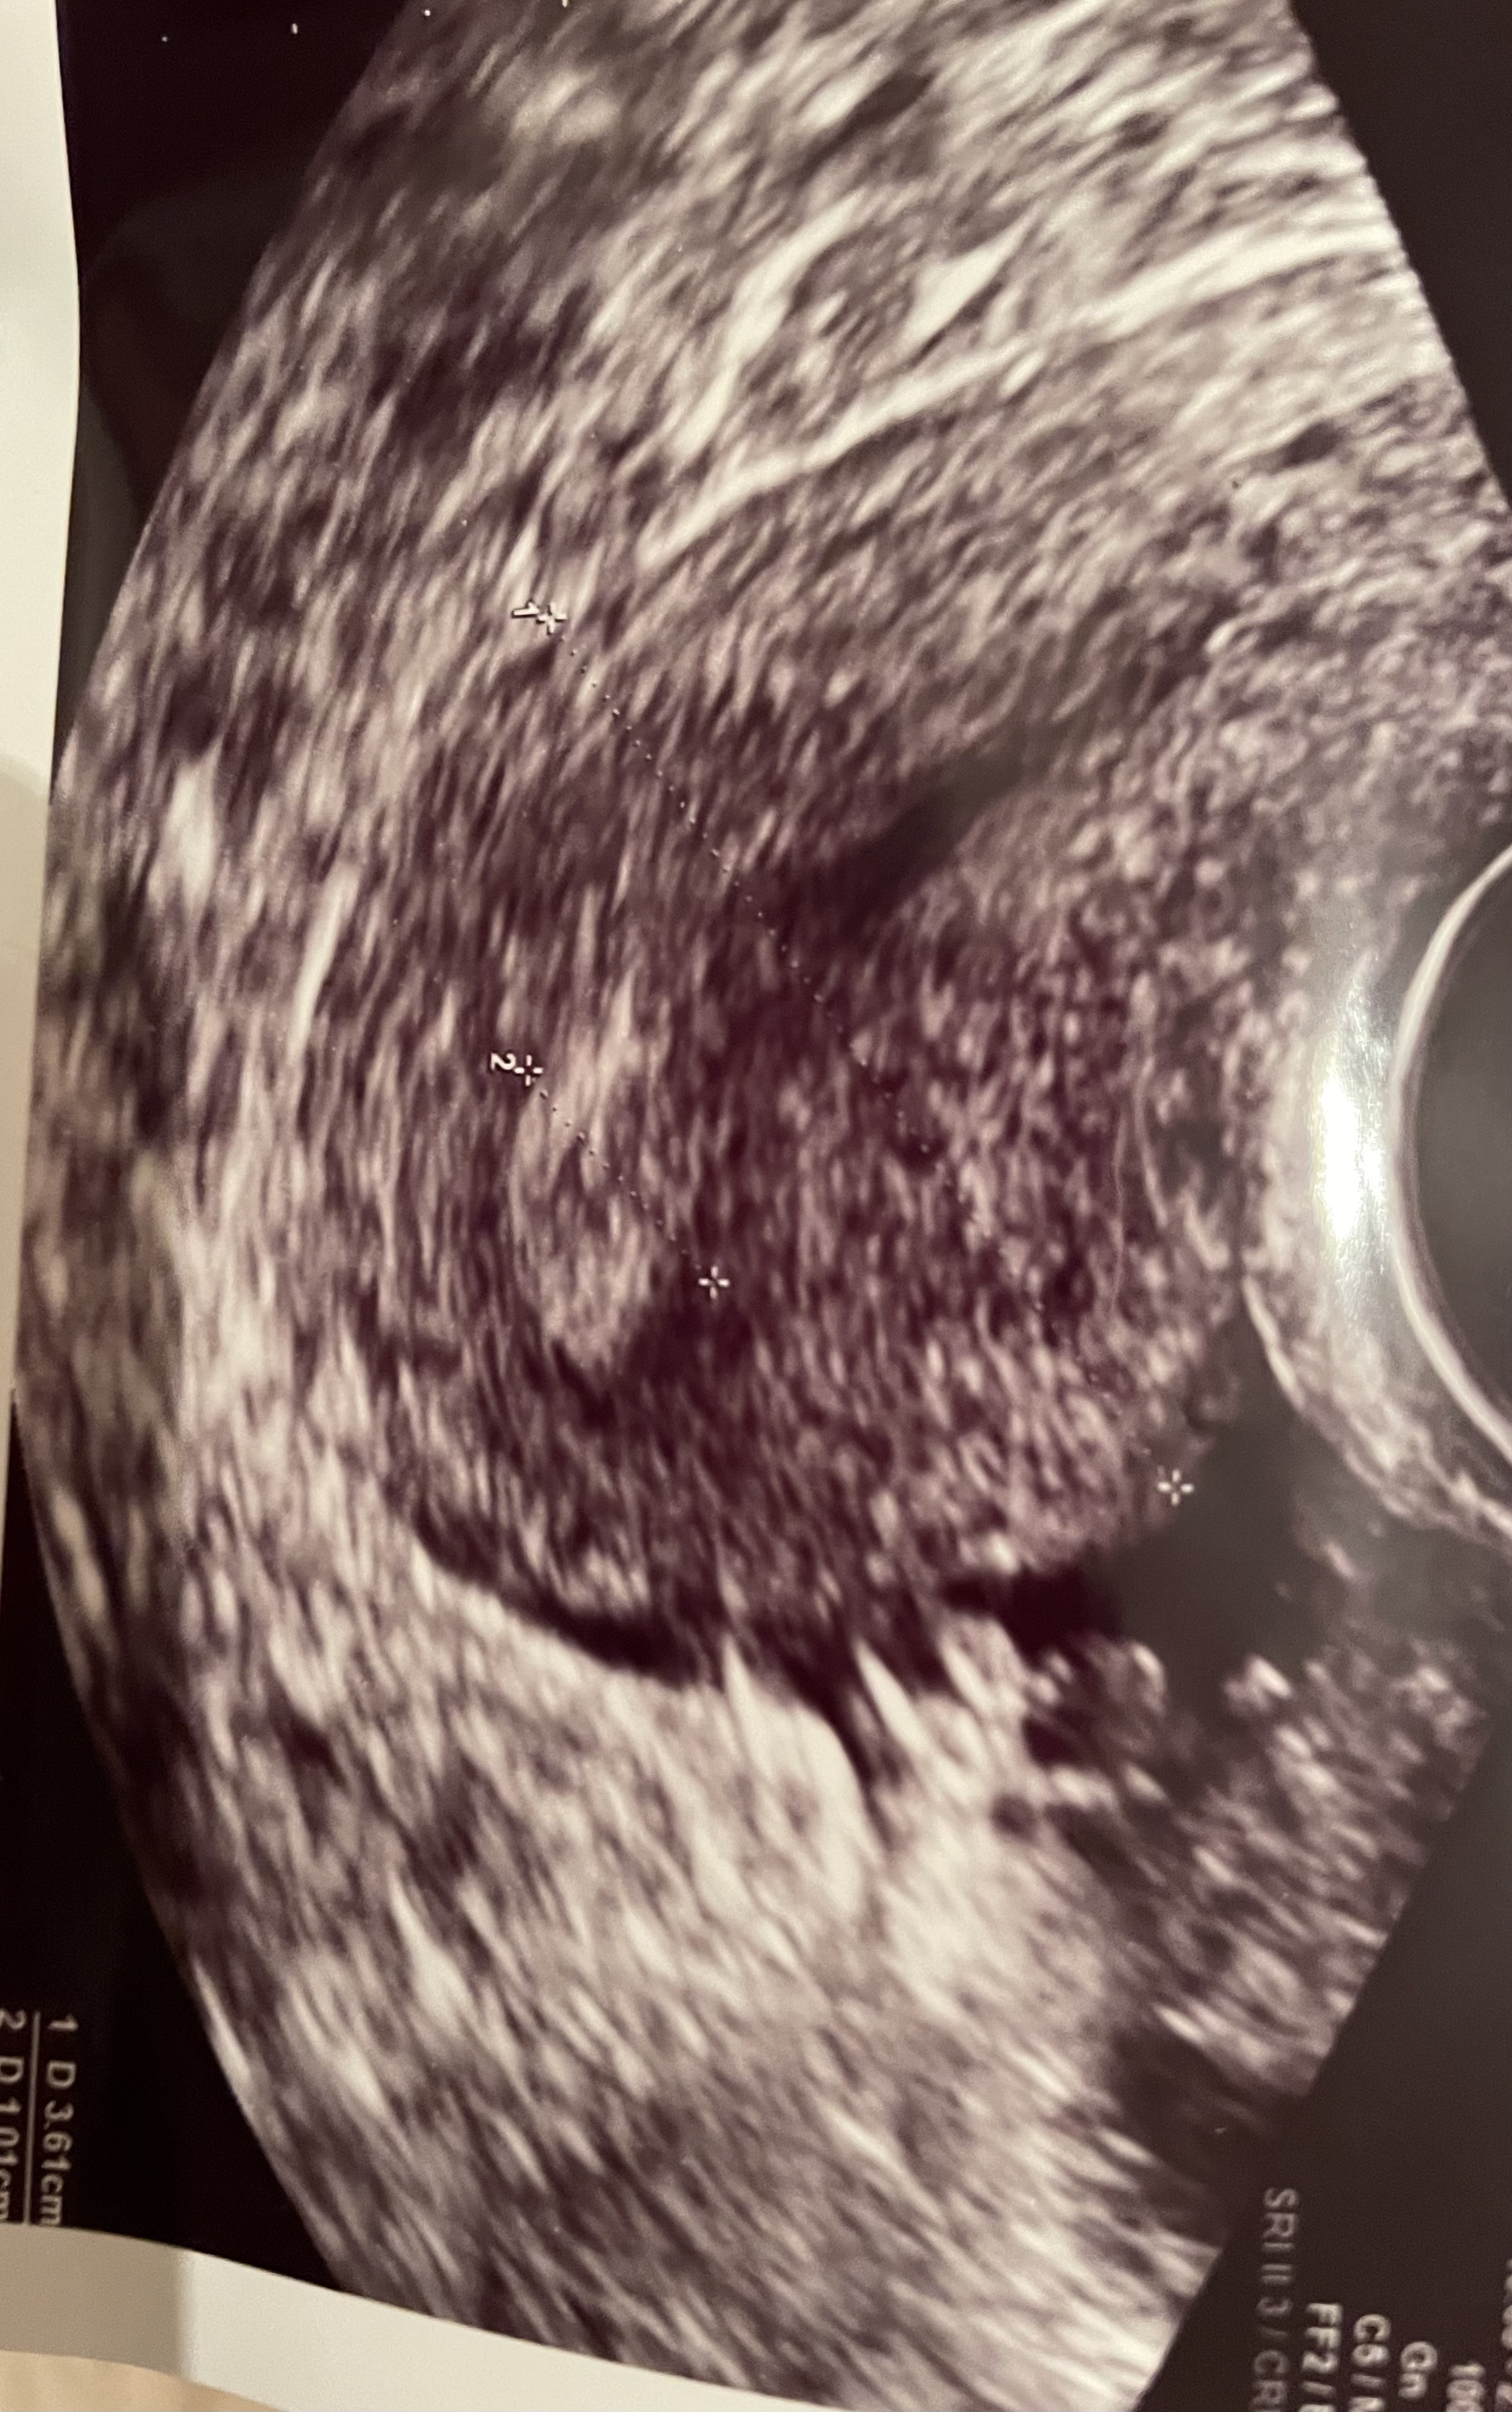

Okres dalej się nie pojawił, lekarz nie wie dlaczego. Po badaniu stwierdził ze jest płyn poza jajnikiem i nie wie skąd się wziął. Na zdjęciu macicy wydaje mi się ze widzę mały pęcherzyk ale lekarz się do tego nie odniósł. Kazał iść na betę bo może być to ciąża pozamaciczna. Jeśli beta wyjdzie ujemna to będę zagadka. Rozkładam już ręce. Czy ktoś tez widzi ten pęcherzyk czy to już tylko moje fanaberie ? Pozdrawiam

• 6DEED944-B97E-4216-9846-C98BB6D067A4.jpeg

6DEED944-B97E-4216-9846-C98BB6D067A4.jpeg

1,4 MB · Wyświetleń: 216